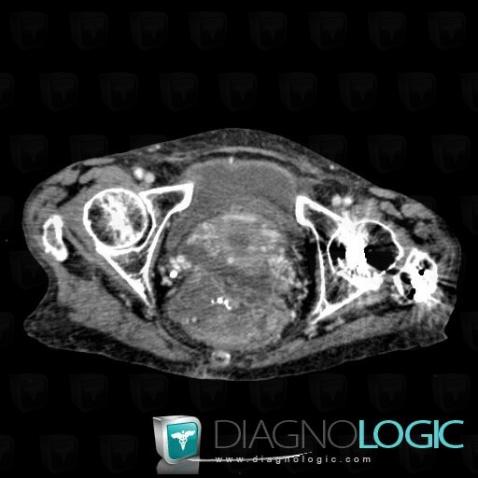

Sigmoid cancer, Pelvis / Perineum, Sacrum / Coccyx, CT

Here is the specific information in the key image above:

- Diagnosis Sigmoid cancer (link to Colon cancer), Location(s) Sacrum / Coccyx, with gamuts Presacral massPelvis / Perineum, with gamuts Presacral mass